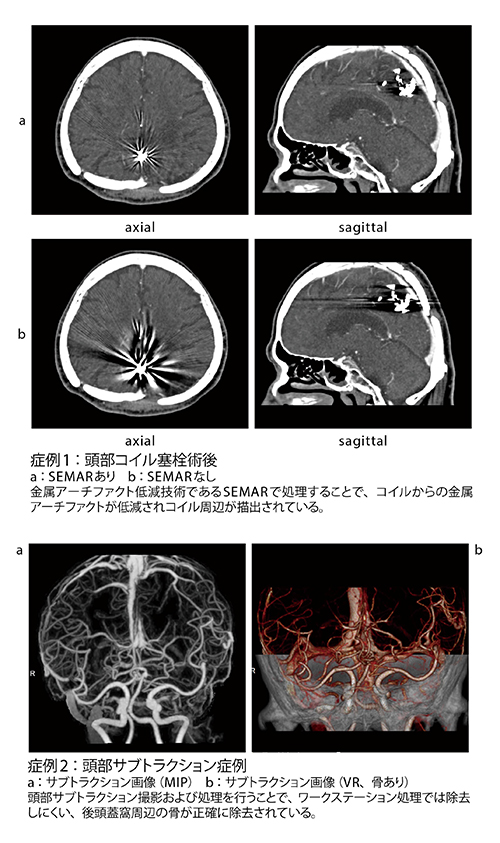

Aquilion Lightningでは、金属アーチファクトを除去する画像再構成技術であるSEMARが標準搭載されている。同クリニックでは、脳動脈瘤のクリッピング術後のフォローアップの際にSEMARを用いた検査を行っている。大西技師長は、「クリップ留置後の検査では、金属アーチファクトの影響で観察可能な画像が得られにくかったのですが、SEMARによってアーチファクトが軽減され評価が可能な画像が提供できるようになりました。義歯の種類や位置によって、アーチファクト低減が異なるため、今後、撮影方法の検討を行う予定です」と述べる。また、頭部造影CTでは、単純と造影撮影の差分から画像を再構成するサブトラクション撮影を行っている。大西技師長は、「Aquilion Lightningでは高い精度のサブトラクションにより、WSでは処理がしにくい後頭蓋窩領域の骨除去が可能で良好な画像が得られています」と述べる。

■Aquilion Lightningによる臨床画像

Aquilion Lightningによる臨床画像